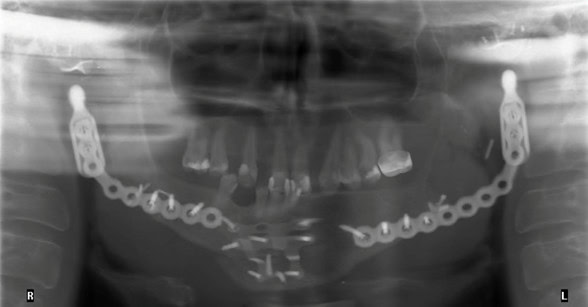

The patient endured two previous TMJ reconstruction attempts, each providing various issues over time. Due to multiple attempts at placing a permanent TMJ prosthesis, excessive amounts of soft tissue scarring was noted and contributing to limited opening. As a result, the patient displayed chronic poor hygiene and caries due to limited access, pain on brushing and a near lack of dental follow-up (Fig. 1). The patient was seen by prosthodontics for a ‘hand-and-mirror’ exam one day prior to full mouth extractions. The patient opted for full mouth extractions due to caries and consistent odontogenic pain. Prosthodontics determined the maxillary cuspids (#6 and #11) should remain since periodontally probing depths ranged from 1- 3mm and caries present were not excessive in depth. Following this prosthodontic consultation, the patient had the remaining dentition extracted excluding #6 and #11.

Figure 1: Panoramic radiograph of the initial patient presentation to the oral surgery department.